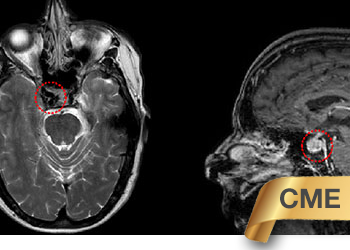

Brain:

Brain Metastasis

Author: Michael Brisman M.D., F.A.C.S., Read More!